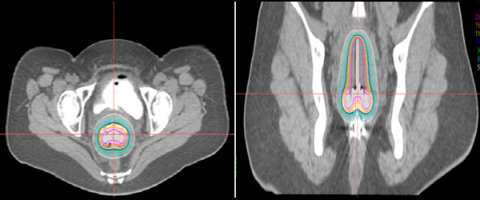

axial image

An example of 3D based planning with an axial image on the left and a coronal image on the right.